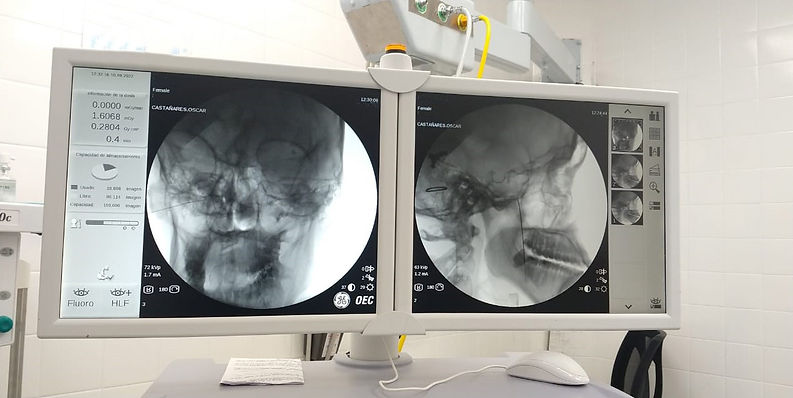

Es el caso de una joven paciente de 16 años con una Cefalea Tensional, refractaria a todos los tratamientos, quien después de 10 años logró disminuir el dolor, luego del procedimiento detallado a continuación.

A esta paciente se le realizó un bloqueo diagnóstico terapéutico de ganglio esfenopalatino derecho, bajo fluoroscopía. Cabe destacar que esta técnica es del Dr. Juan Carlos Flores del Centro de Atención Integral del Dolor Buenos Aires (CAIDBA).

Luego de emplear dicha técnica, la paciente por primera vez en diez años dejó de sentir dolor.

El Dr. Oscar Castañares destacó “por primera vez la vi sonreír desde la que la trato hace unos años”.